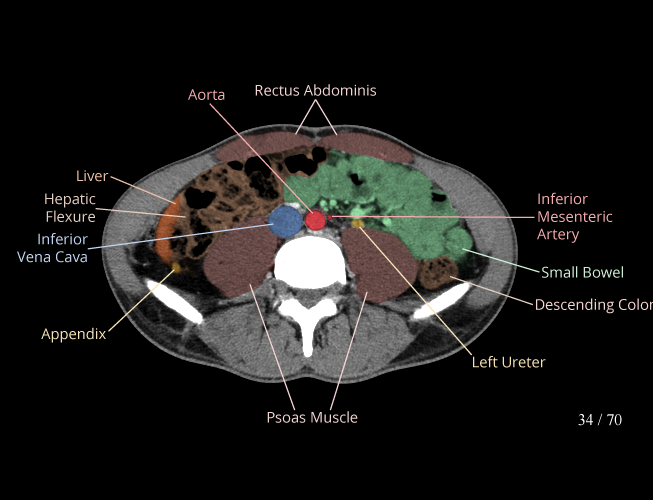

Body

Covers abdominal CT anatomy.